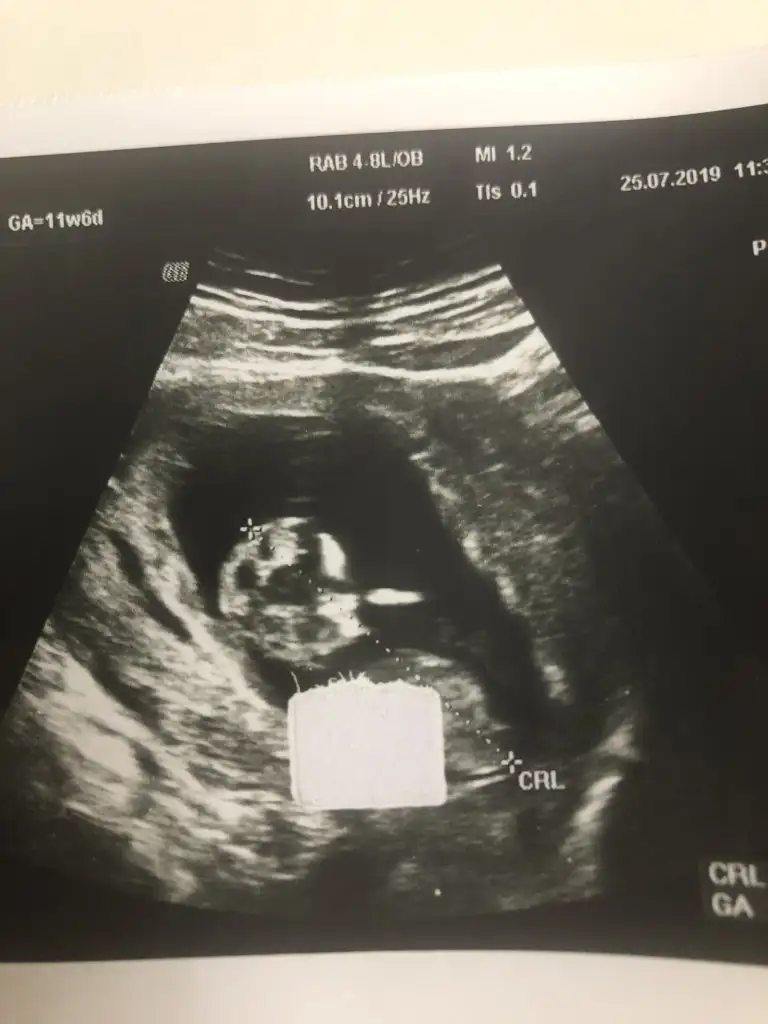

Bunlarda az önce alınan resimler normalde 11 hafta 6 günlük ama usg de 12 hafta 6 günlük

Siz erkek istiyordunuz galiba.nub çizgisine ve kafa yapısına göre yorum yapıyorum.cinsiyet oluşmadan önce nub çizgisi oluşur.bu çizgi paralelse kız,dik ise erkek demektir.sizin bebeğinizin nub çizgisi bariz paralel.kafa yapısı da oval.erkeklerin kafa yapısı daha yuvarlak olur. Doktor kesin erkek dedi mi size? Buda cinsel organı diye gösterdi mi? Kaç haftalıksınız şuan?Doktor organını bile gösterdi bu çıkıntı olabilir diye yine de cevabınız için teşekkür ederim merakımdan soruyorum yanlış anlamayın neye göre Tahminde bulunuyorsunuz mesela son resim tam olarak neyi gösteriyor hiçbirşey anlamadım

Evet gönlümden geçen erkek Bi tane kızım var çok ta sevinmiştim siz şimdi kesin kız deyince moralim bozuldu biraz. Şu an sat a göre 11 hafta 6 gün usg ye göre 12 hafta 6 gün. Doktor erkeğe çok benziyor çıkıntısı burada diyerek gösterdi kesin erkek demedi yüzde 80 erkek dedi ama bazen kızlarda da bu çıkıntı oluyor dedi. Hatta bu Nub teorisinden de bahsettim belli olmaz bazen dik bazen paralel bile olabilir dediSiz erkek istiyordunuz galiba.nub çizgisine ve kafa yapısına göre yorum yapıyorum.cinsiyet oluşmadan önce nub çizgisi oluşur.bu çizgi paralelse kız,dik ise erkek demektir.sizin bebeğinizin nub çizgisi bariz paralel.kafa yapısı da oval.erkeklerin kafa yapısı daha yuvarlak olur. Doktor kesin erkek dedi mi size? Buda cinsel organı diye gösterdi mi? Kaç haftalıksınız şuan?

Kızlarda da bu çıkıntı oluyor dediyse nub çizgisinden bahsediyor.11 12 haftada cinsel organ tam anlamıyla oluşmuyor nub çizgisi oluyor.13 14 haftalarda organ oluşmuş oluyor.yani direkt olarak pipi göstermemiş.bilmiyorum doktor erkek dediyse erkek olabilir.ben bariz kız görüyorum bu usg de.elbette doktorlar daha iyi bilir tabi.rabbim gönlünüzdekileri nasip etsin inşallah.siz sorduğunuz için cevapladım.ama bana göre bu bebiş kızEvet gönlümden geçen erkek Bi tane kızım var çok ta sevinmiştim siz şimdi kesin kız deyince moralim bozuldu biraz. Şu an sat a göre 11 hafta 6 gün usg ye göre 12 hafta 6 gün. Doktor erkeğe çok benziyor çıkıntısı burada diyerek gösterdi kesin erkek demedi yüzde 80 erkek dedi ama bazen kızlarda da bu çıkıntı oluyor dedi. Hatta bu Nub teorisinden de bahsettim belli olmaz bazen dik bazen paralel bile olabilir dedi